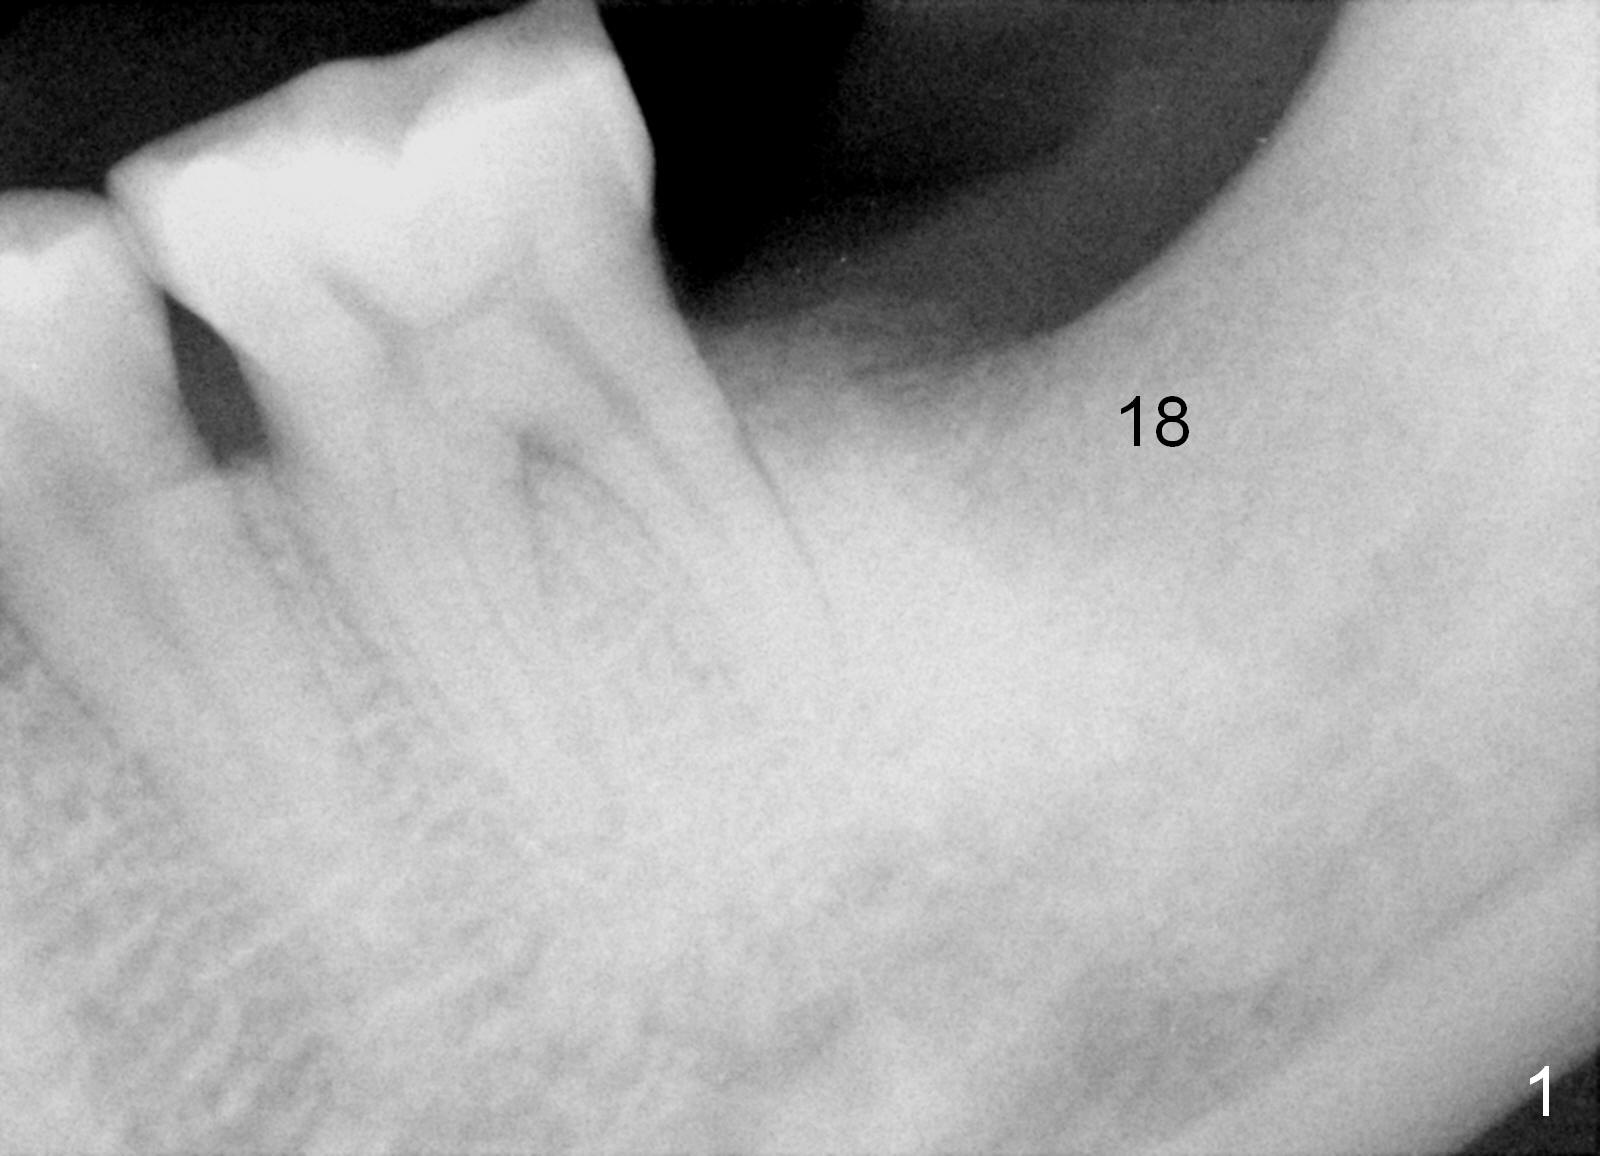

A 37-year-old man has history of chronic periodontitis. He returns for #18 implant placement 4 months post extraction (Fig.1). A 6x14 mm tissue-level implant is placed using combination of bone expansion and drills (Fig.2). Fig.3 shows the implant 5 months postop.